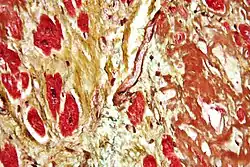

Histopathology

Histopathology refers to the microscopic examination of various forms of human tissue. Specifically, in clinical medicine, histopathology refers to the examination of a biopsy or surgical specimen by a pathologist, after the specimen has been processed and histological sections have been placed onto glass slides.[17] This contrasts with the methods of cytopathology, which uses free cells or tissue fragments. Histopathological examination of tissues starts with surgery, biopsy, or autopsy. The tissue is removed from the body of an organism and then placed in a fixative that stabilizes the tissues to prevent decay. The most common fixative is formalin, although frozen section fixing is also common.[18] To see the tissue under a microscope, the sections are stained with one or more pigments. The aim of staining is to reveal cellular components; counterstains are used to provide contrast. Histochemistry refers to the science of using chemical reactions between laboratory chemicals and components within tissue. The histological slides are then interpreted diagnostically and the resulting pathology report describes the histological findings and the opinion of the pathologist. In the case of cancer, this represents the tissue diagnosis required for most treatment protocols.